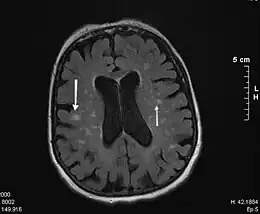

IRM : lésions vasculaires multiples disséminées (flèches).

L'imagerie par résonance magnétique (IRM) en phase T2, et la tomodensitométrie (scanner) montrent la présence de lésions de la substance blanche, disséminées dans le cerveau ; ces images, sous forme d'un hypersignal, témoignent des lésions vasculaires. Ces lésions vont plus ou moins confluer avec l'évolution de la maladie et aboutir à donner une image de « cerveau en gruyère ».